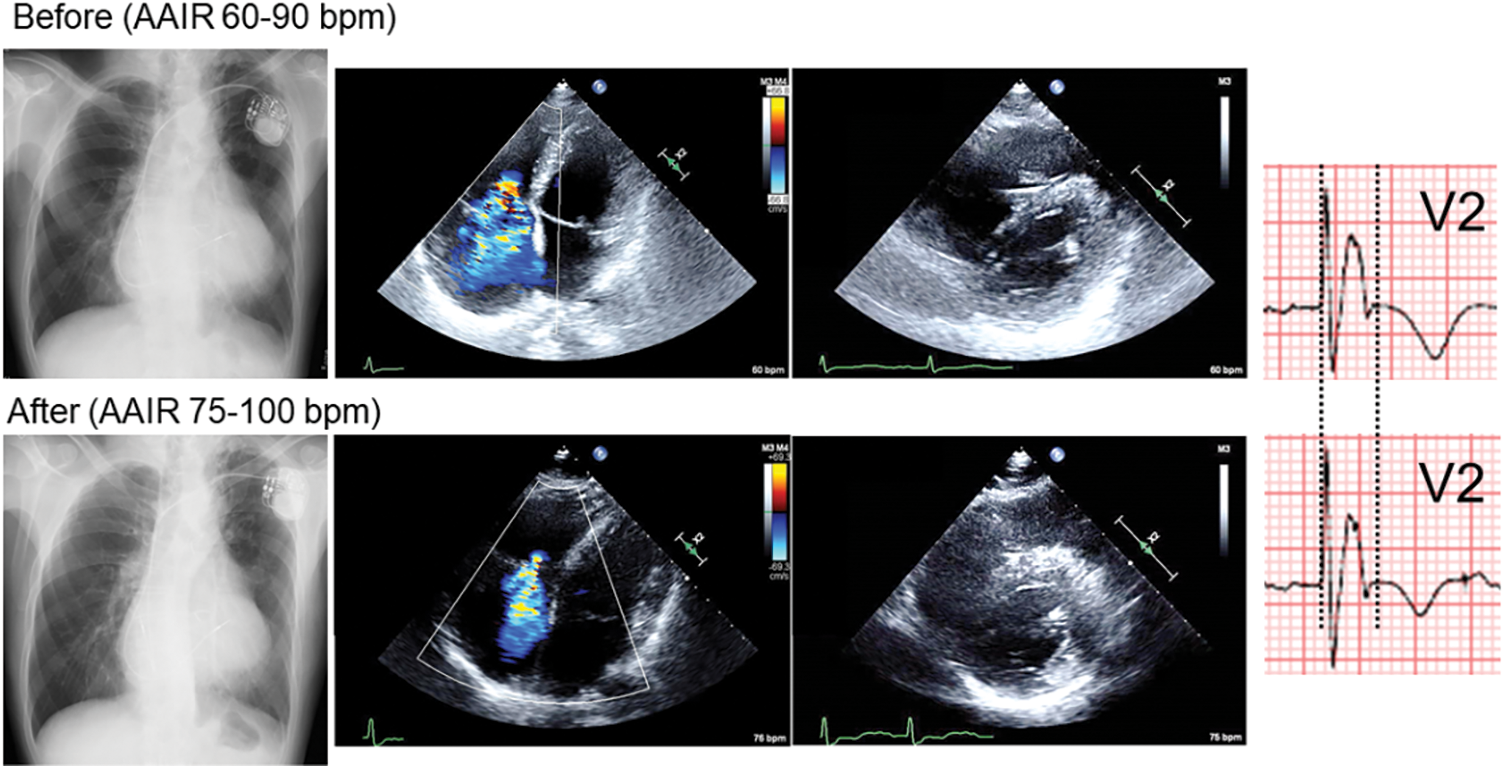

Figure 1: Chest X-ray, 4-chamber and short-axis echocardiography, and electrocardiogram in V2 before and 4 months (Chest X-ray, Echocardiography) or 6 months (electrocardiogram) after changing pacemaker lower rate from 60 to 75 bpm

After the recent episode of heart failure, we changed the setting of managed ventricular pacing up to 75–100 bpm. Also, home oxygenation therapy was commenced. Eventually, his heart failure symptoms gradually improved (down to NYHA class II) on the same dose of anti-heart failure drugs (Fig. 3). SpO2 came up to 91%–97% in room air. He now enjoys taking a walk (6 min walk test; 384 m with room air). Atrial tachyarrhythmias are under control with a smaller dose of amiodarone. The serum level of the brain natriuretic peptide, cardiothoracic ratio on chest X-ray, and QRS duration on electrocardiogram changed favorably (Figs. 1 and 2). Tricuspid regurgitation and diastolic leftward shift of the ventricular septum improved (Fig. 1).